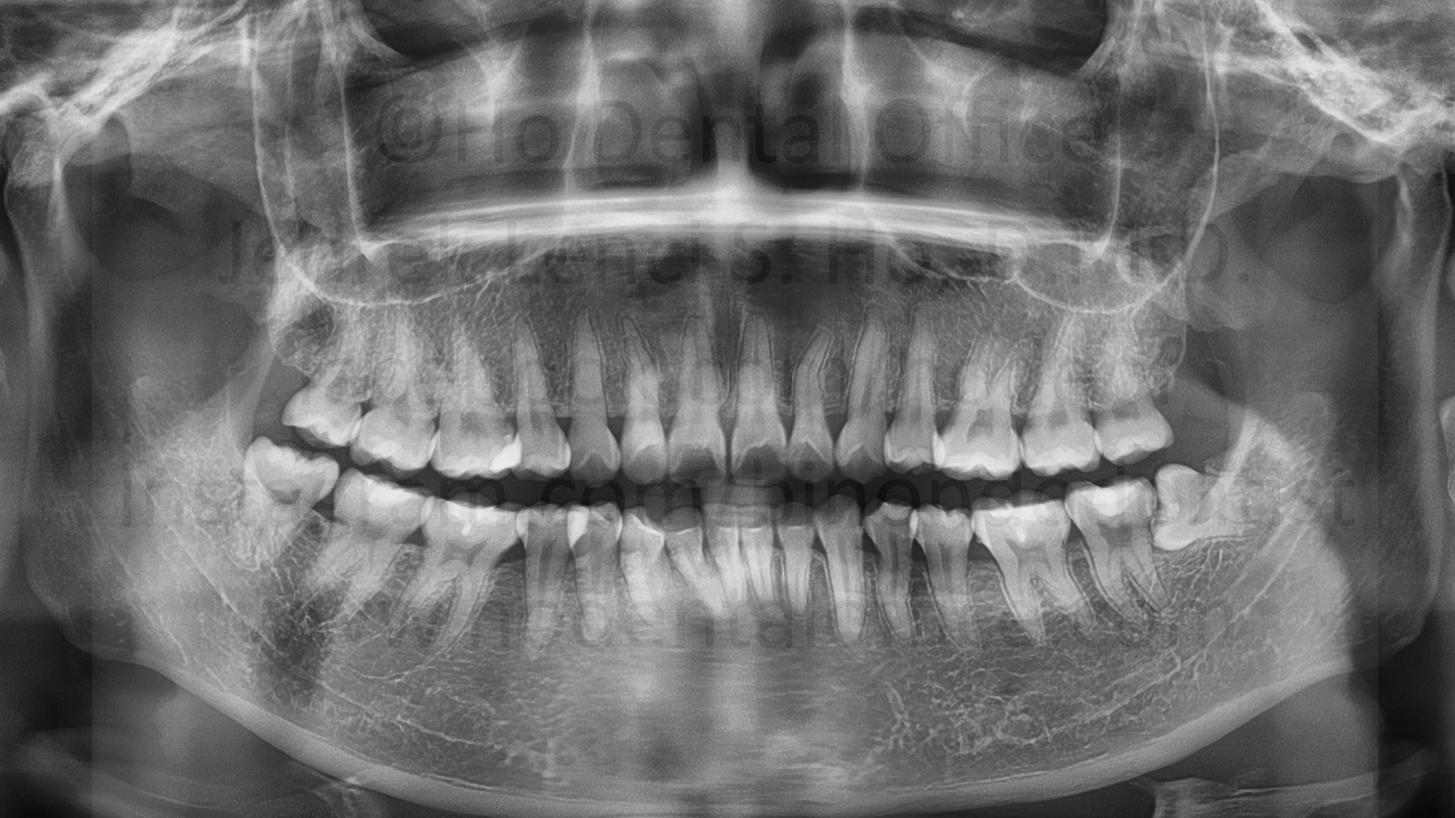

- prevention of periodontal disease - Periodontal pockets may develop from frequent food impaction. This may lead to further gingival attachment loosening ("flabby gums") which will again lead to more food impaction. As periodontal disease progress, it will eventually erode healthy bone and loosen tooth.

![]() |

![]() | ![]() | ![]() |

| bone loss due to presence of third molars, note the bone level of the second molar on the side facing the third molar is already on the level of the second molar's roots | ||